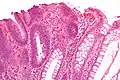

| Трубчатая аденома | Трубчатые железы с удлинёнными ядрами (как минимум незначительная атипия) | Да | ![]() |

|